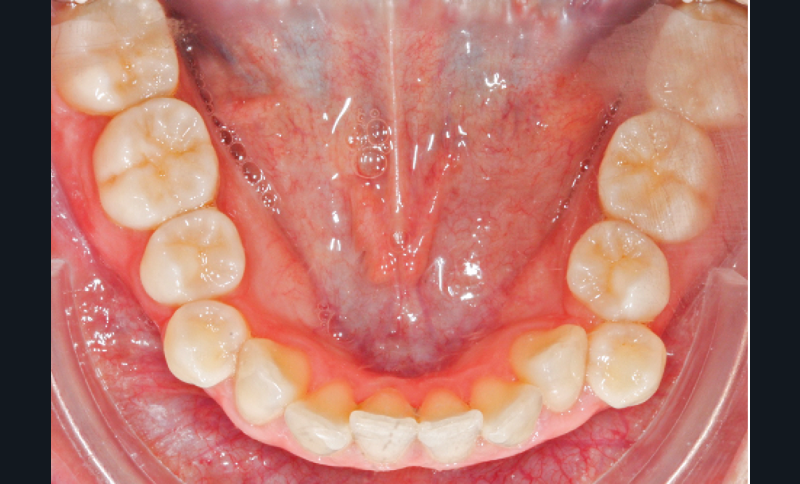

L’examen intra-arcade met en évidence une hygiène bucco-dentaire irréprochable, favorable à un traitement en technique linguale. Le phénotype parodontal est fin dans la région incisivo-canine mandibulaire. L’encombrement est estimé à 8 mm à la mandibule et à 4 mm au maxillaire (fig. 1). Les arcades ont des formes similaires, en U. Les rapports inter-arcades mettent en évidence une classe 1 d’Angle molaire, une classe 2 d’Angle canine et une supraclusion antérieure (recouvrement : 5 mm ; surplomb diminué). Les milieux inter-incisifs sont déviés entre eux avec une origine mixte (= 1,5 mm) (fig. 2).